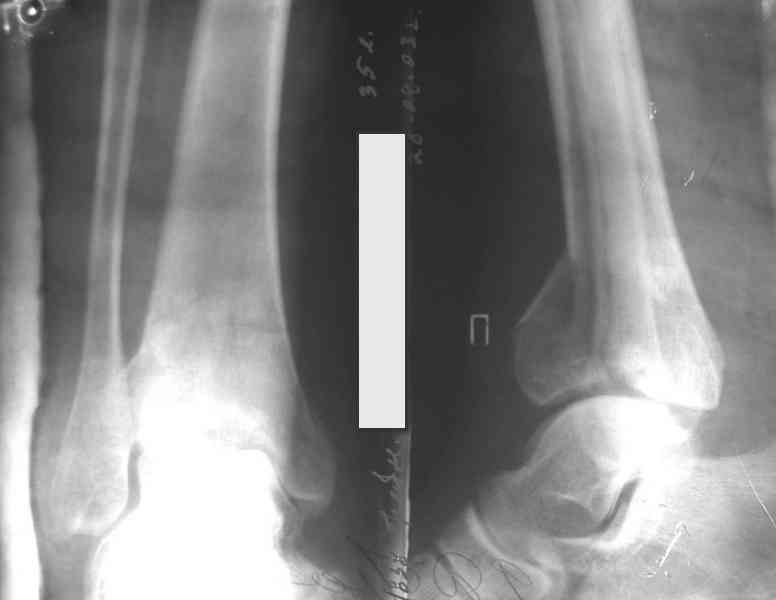

На рентгенограммах типичный перелом пилона по типу С-3. есть опыт до 100 открытых опреаций у нас в клинике. 20 примерно в год. Принцип один -все внутрисуставные переломы нуждаются в открытой репозиции и внутренней стабильной фиксации. При поступлении КТ не надо, так как получается только нагромождение костей. Истинной картины нет. Главное восстановить длину малоберцовой кости - это ключ к успеху. При поступлении меньше всего надо думать о сосудистых расстройствах, т.к. сама операция и репозиция даже сначала частичная даёт улучшение сосудитых нарушений. Причём очень быстро. Операция в 2этапа. При поступлении доступ позади наружной лодыжки, причём обязательно. После этого репозиция малоберцовой кости и фиксация пластиной 1/3 трубки под винт 3,5. Дренаж и любой аппарат наружной фиксации. Затем после спадения отёка на 5-7-10 день аппрат снимается и дугообразный разрез спереди от медиальной лодыжки 10-12 см. Главной чтобы расстояние между 1 и вторым разрезом было не меньше 7-8 см. Тогда не будет некрозов лоскутов. Таранная кость используется как матрица на неё укладываются отломки и фиксируются пицами. Ренг-контроль. Отломки лежат все отдельно, но ничего не высыпется. При переломах С-3 всегда нужна костная пластика (из крыла). Фиксация пластиной лист клевера простой или LCP. Гипс не нужен. Дренаж до 48 часов. Операция длится 3-4 часа обязательно без жгута. Посылаю примерно такой же случай.

Отправитель: Дрягин В. 04 Январь 2007, 09:00

Ещё есть одна проблема когда есть перелом малоберцовой кость, то всё ясно. А когда малоберцовая кость не повреждена, то сразу накладывается аппрат наружной фиксации при поступлении, чтобы как бы перерастянуть отломки и главное убрать вальгусное или варусное смещение, а потом на 5-7 день открыто большеберцовая кость восстанавливается и фиксируется пластиной. С уважением Дрягин